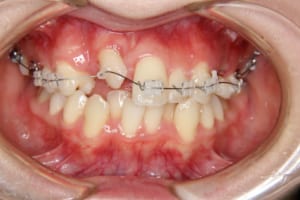

治療前

治療中

治療内容 唇側矯正装置を使用した成人矯正治療を行いました。

使用した装置 マルチブラケット装置(唇側矯正)

InVuブラケット

シルバーワイヤー

ホールディングアーチ

歯科矯正用アンカースクリュー(1本)

その他/備考 上顎右側中切歯および側切歯が、埋伏していた犬歯によって歯根吸収していました。

牽引に半年かかりました。